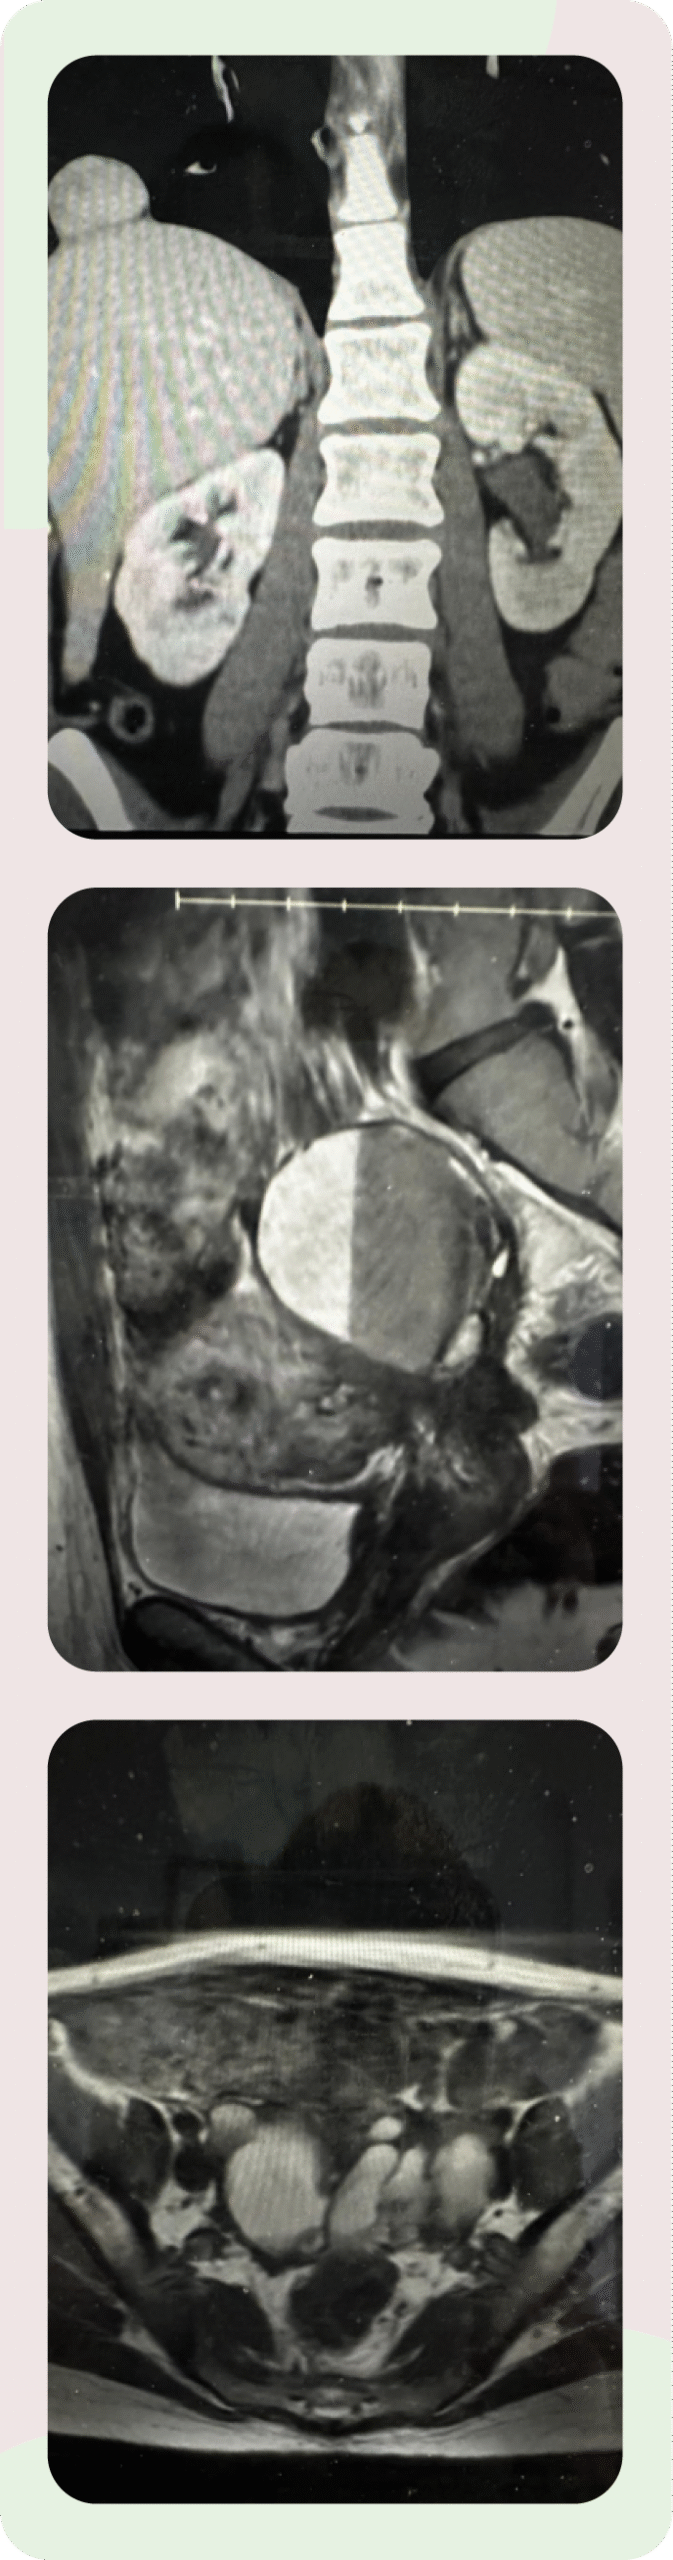

The doctors at ESSE Care are skilled surgeons and medical professionals, but listening may be their most important skill. During Anne’s consultation, Dr. Goldstein asked questions and suggested diagnostics that seemed obvious in hindsight but no other provider had suggested, including follow-up scans of her pelvis and abdomen to see whether anything was obviously wrong—with her endometriosis or otherwise.

What the scans found was shocking:

- A partially collapsed lung

- Her liver herniated into the thoracic cavity through a hole in the diaphragm

- Endometriomas throughout the pelvis

- Masses on the bladder and ureters

- The bowels and ovaries fused to the uterus (“frozen pelvis”) and the cul-de-sac region obliterated.

Dr. Goldstein instantly recognized the signs of severe, stage 4 pelvic endometriosis as well as thoracic endometriosis. The most urgent need was to reinflate Anne’s lung with a chest tube and allow it to heal. Dr. Goldstein coordinated care with a nearby hospital for the chest tube procedure, then scheduled endometriosis excision surgery for the following week.